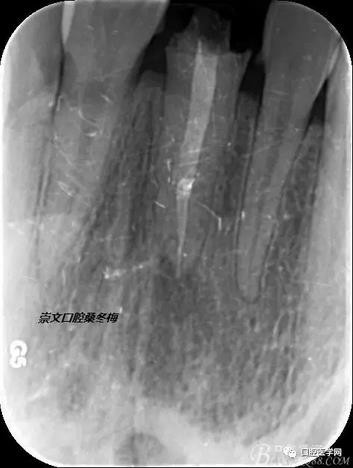

輔助檢查:X線見根尖區(qū)輕低密度影像,根尖1/3見根充物密實恰填,根管上2/3見折斷纖維樁,與根管密實。

術(shù)前X線片